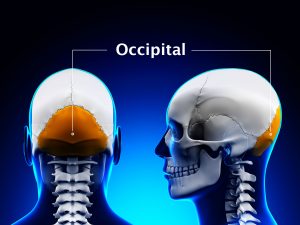

Whereas acute stress resulting from trauma may temporarily block pain, chronic physical or emotional stress can cause pain and lowering your tolerance to pain, stress makes existing discomfort worse. For example, if you are worried that pain results from a serious disease, it may be hard to bear, but once you know that this is not the case, you may find the pain much more tolerable. Long-term stress also causes physical tension, which makes you prone to headaches and minor injuries, such as strained muscles.